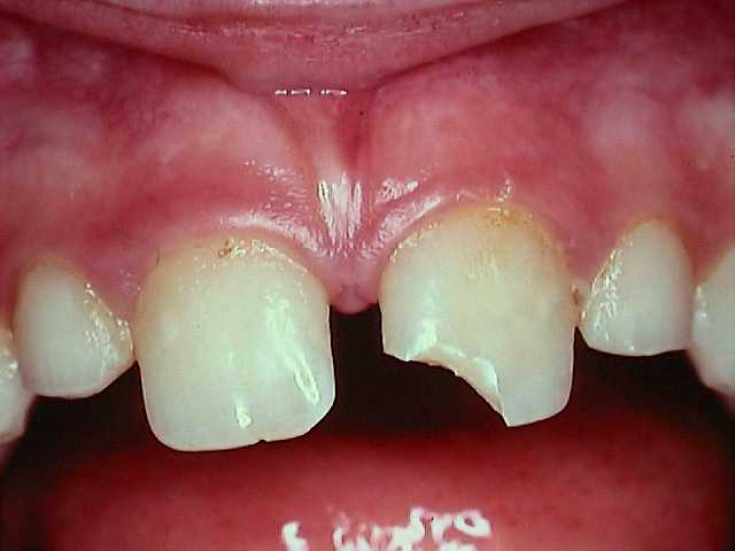

3. Fracture

– root fracture, damage to the integrity of the pulp. The sharp edges of a broken tooth scratch the mucous membrane of the mouth, cheeks, and tongue. During biting, a sharp sharp pain is felt that does not go away. An immediate appeal to a doctor who will conduct endodontic diagnostics is required.